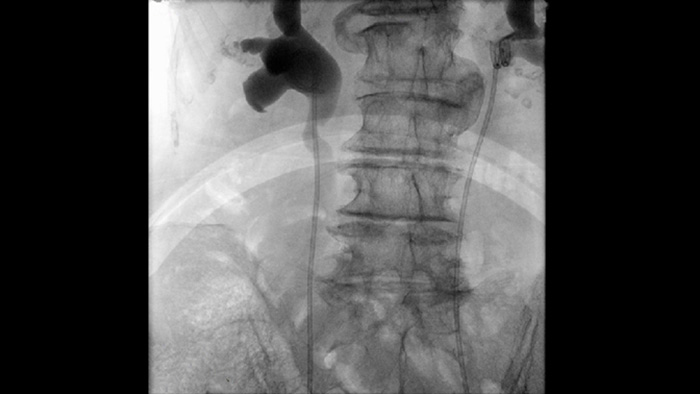

A fluoroscopia pulsada melhora a imagiologia de anatomia densa e complexa para o apoiar na gestão da dose. Pode selecionar uma gama de frequências de pulsação de fluoroscopia para reduzir a dose quando pretendido ou para melhorar a qualidade da imagem conforme necessário.

Parâmetros de imagiologia predefinidos para diferentes procedimentos e anatomia, que podem ser personalizados de acordo com a aplicação, aumentam a confiança clínica e a eficiência para os diversos procedimentos e pacientes.